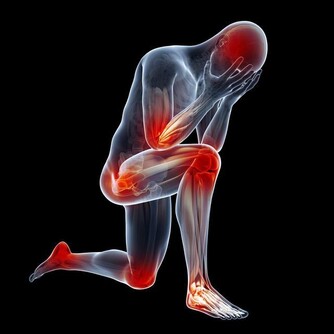

3、損傷腎臟

痛風患者體內的尿酸比較高,大量的尿酸鹽在腎臟內沉積,最終導致腎病變。據WHO統計,1/4的痛風患者會出現腎功能衰竭,發展為嚴重的尿毒症。

4、痛風石

痛風石的形成是長期高尿酸血症引起的組織損傷的結果,是痛風的特徵性病變;沉積在關節囊,影響關節活動;可導致骨“鑿孔”樣損害,嚴重者可導致骨折。關節脫位及畸形;痛風石破潰後,不易癒合,極易導致截肢悲劇。